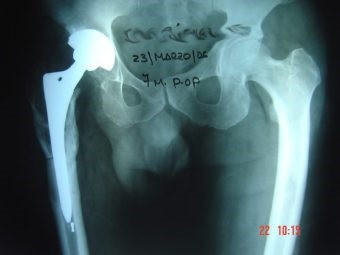

Prótesis Total de Cadera

Envíado por Dr. Ricardo Antonio Gómez G.